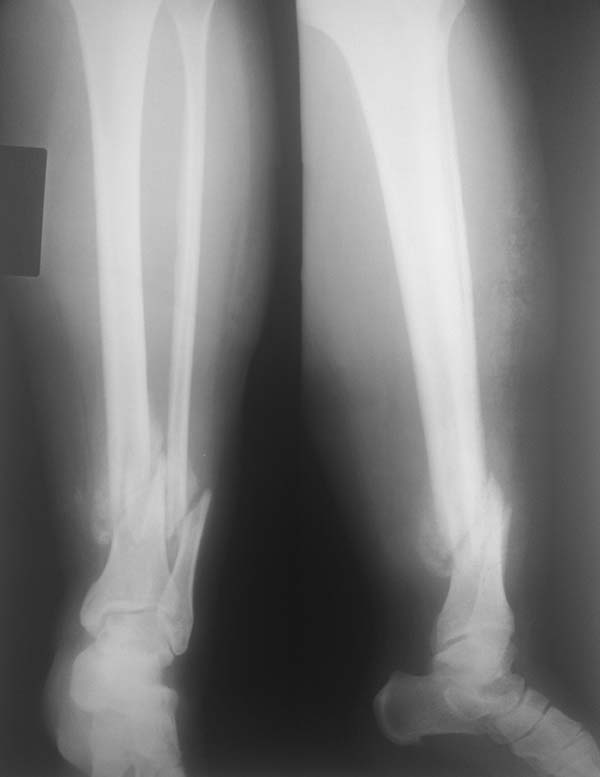

Неправильно консолидирующий оскольчатый перелом нижний трети костей голени.

Коллеги, поступил пациент 55 л, с диагнозом: Неправильно консолидирующий оскольчатый перелом нижний трети костей голени.

Жалобы на боль, отечность и нарушение опороспособности. 3 месяца назад получила бытовую травму. В свизи с снежной зимы не мог выехать из села, лечилась у костоправа. При осмотре имеется умеренная угловая деформация, отечность, наступать не можеть из за боли.